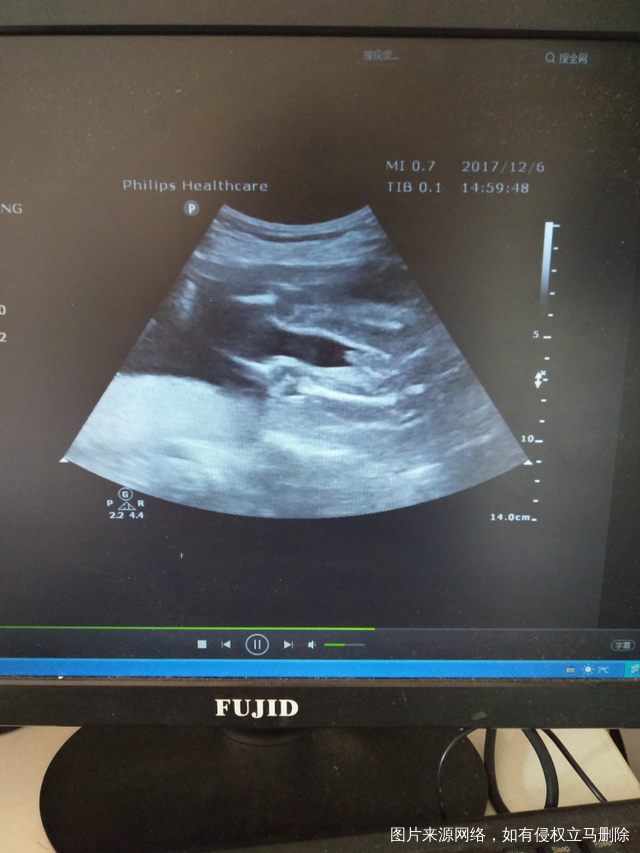

有宝宝的性器官图片 只是我还看不懂?有经验的宝妈可以帮我看一下

吗?